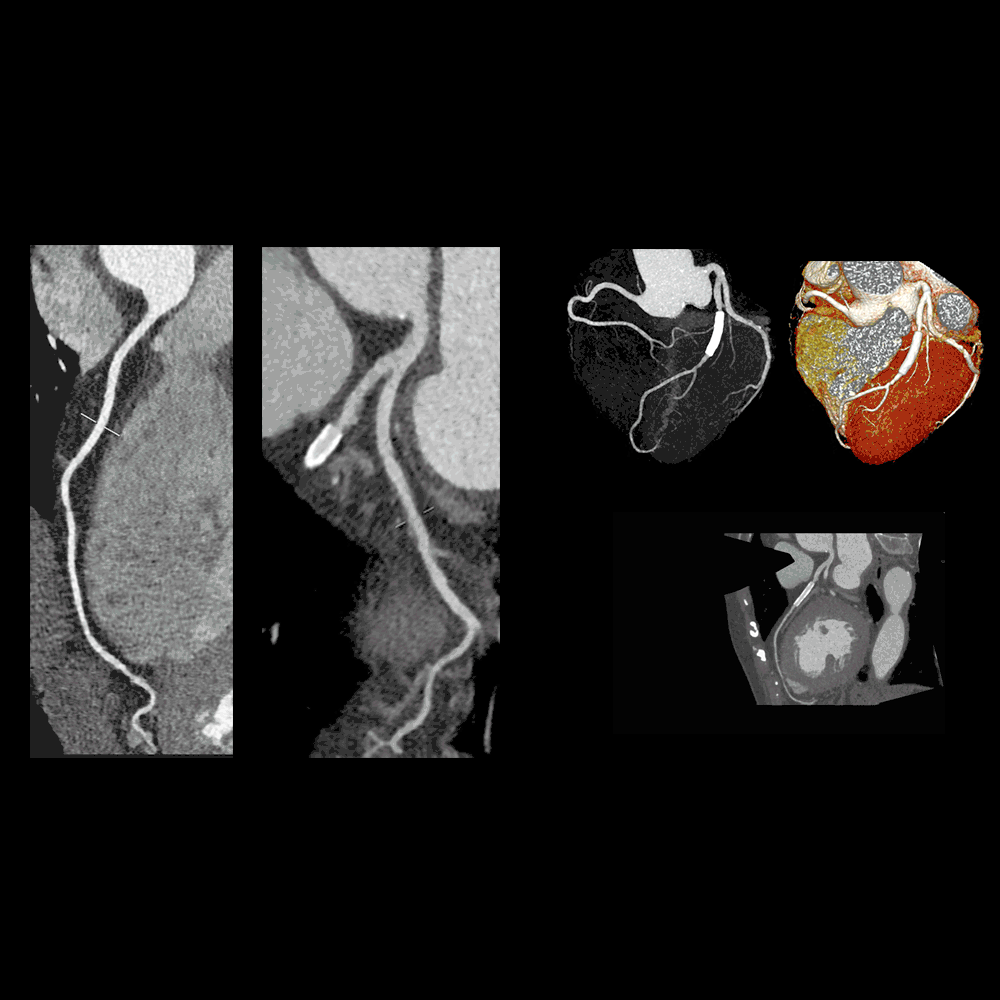

Heart Stent Gif. Find the gifs, clips, and stickers that make your conversations.  — an excerpt of the video created for one of our clients.this medical.  — if you have heart disease, your doctor may recommend that you undergo a procedure called stenting.  — the heart stent procedure. a stent is a tiny wire mesh tube that keeps a coronary artery open to increase blood flow to the heart. If the blockage is not major, the. browse makeagif's great section of animated gifs, or make your very own. It can also be used to improve blood flow. a coronary angioplasty is a procedure used to widen blocked or narrowed coronary arteries (the main blood vessels supplying.  — coronary angioplasty and stent placement can greatly increase blood flow through a previously blocked or narrowed. This reduces the chance of a. Giphy is the platform that animates your world.  — a coronary stent is a small mesh tube that’s inserted into an artery where plaque has built up and narrowed the space for blood flow.  — a heart stent is a tube that is placed in the blocked passage of your heart to unclog it and resume normal blood flow. Giphy is the platform that animates your world.

Heart Stent Gif Mayo clinic news network.learn about coronary.  — if you have heart disease, your doctor may recommend that you undergo a procedure called stenting.  — a cardiac stent is used to treat narrowed or blocked coronary arteries.  — please courtesy:  — an excerpt of the video created for one of our clients.this medical.  — medical animation visualizing the insertion and placement of a. A stent is a thin.  — a coronary stent is a small mesh tube that’s inserted into an artery where plaque has built up and narrowed the space for blood flow. The implantation of a heart stent is a systematic process that involves close.  — this interactive video shows an angiogram and then an angioplasty with. It can also be used to improve blood flow. browse makeagif's great section of animated gifs, or make your very own. our cardiovascular system animations, illustrations and interactive media help hundreds of our clients explain stent implants, balloon catheters, heart. angioplasty is a procedure to open narrowed or blocked arteries caused by deposits of plaque. Upload, customize and create the best. Giphy is the platform that animates your world.